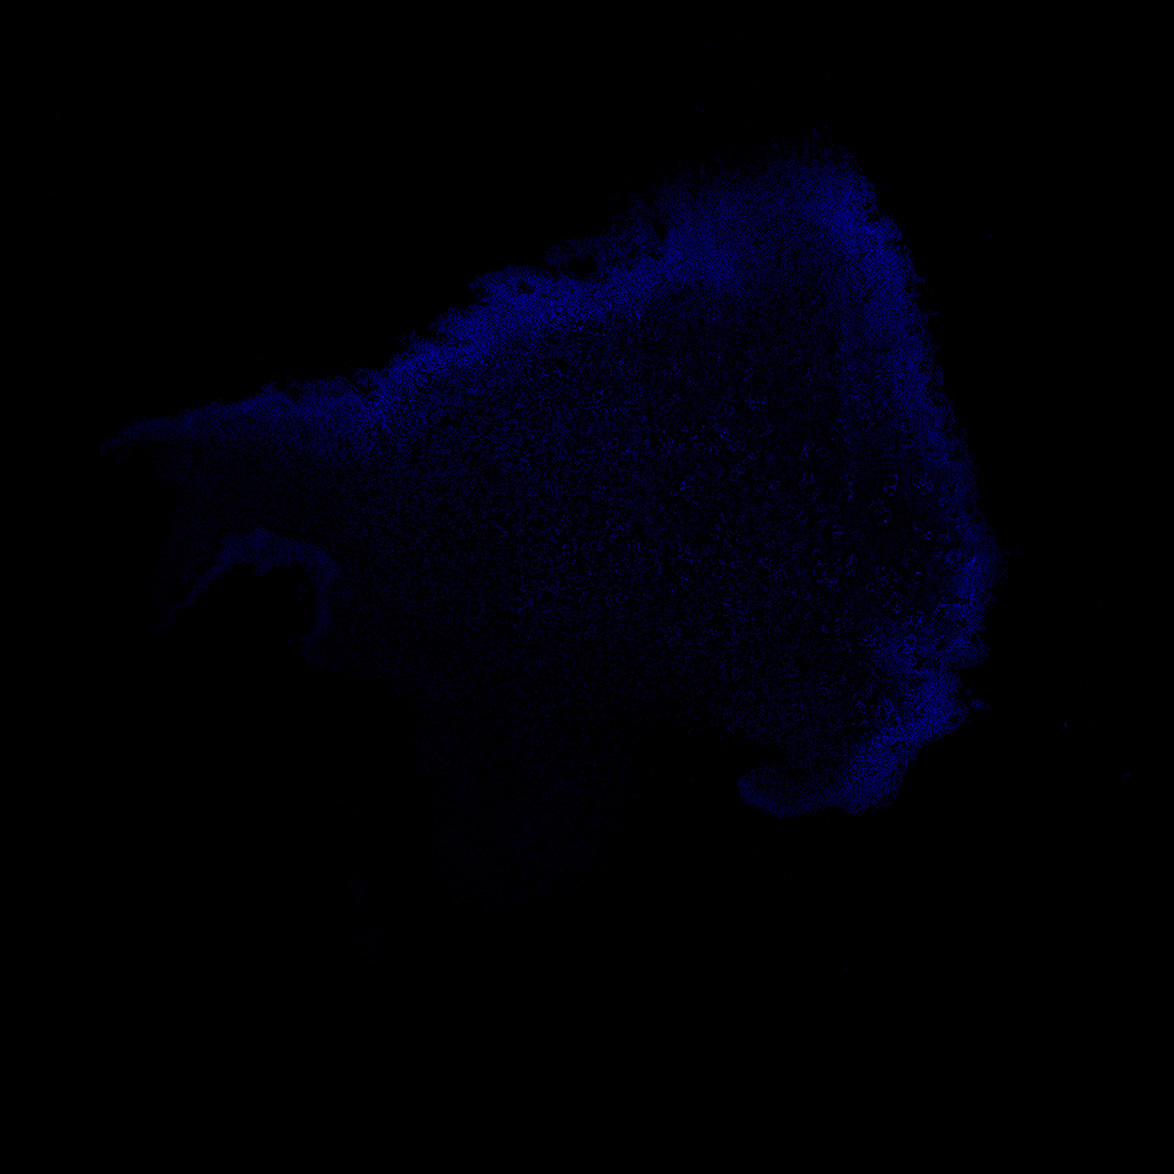

6PCW

DAPI

6PCW human midbrain